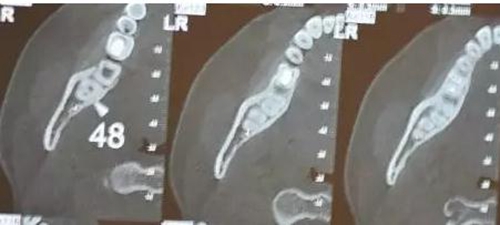

患者、女、24歲,主訴:右側(cè)下后牙自發(fā)疼數(shù)月。專科檢查:48垂直位、萌出約1/2,合面齲壞,探痛明顯,全景片檢查;48牙根與下頜管重疊,加拍CBCT檢查:下頜管位于48根尖下方的舌側(cè),牙根并未進(jìn)入下頜管內(nèi)。診斷:48中位垂直阻生伴牙髓炎。治療計劃:建議拔除48.患者同意治療方案,簽術(shù)前知情同意書。

圖2.術(shù)前全景片檢查:48近中有致密充填影像,雙根、牙根與下頜管重疊。

圖3.術(shù)前CBCT全景片重建影像檢查:48牙根與下頜管重疊

圖4.CBCT的水平斷面檢查:48牙根不在下頜管內(nèi),但與下頜管緊鄰